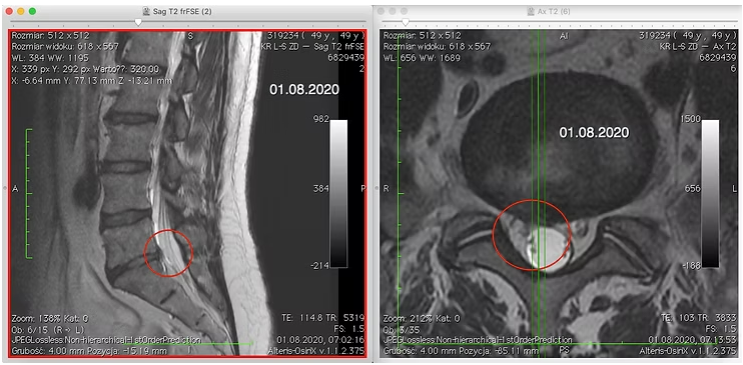

Na kolejnej wizycie otrzymałem od pacjenta świeżo wykonany rezonans magnetyczny lędźwiowego odcinka kręgosłupa, który załączam poniżej (ryc. 2).

Po obejrzeniu badania okazało się, że ogromna część dysk L5-S1 znajduje się w kanale kręgowym wypełniając prawy zachyłek korzenia nerwowego drażni go znacząco.

Czerwonymi strzałkami oznaczyłem przepuklinę dysku (po lewej widzicie kręgosłup widziany od boku – w płaszczyźnie strzałkowej, a po prawej widziany od dołu – w płaszczyźnie czołowej). Jak widać na powyższym rezonansie przepuklina dysku zajmuje większą część kanału kręgowego powodując jego stenozę (zwężenie przestrzeni).